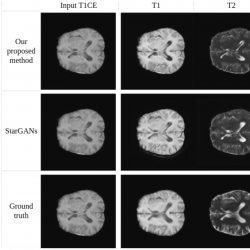

Fig. 19

Synthesis of MRA, PD-weighted and T1-weighted images using a single T2-weighted image as input (IXI dataset).

Fig. 20

Synthesis of T1-weighted, T2-weighted, and FLAIR images using a single T1CE-weighted image as input (BraTS2020 dataset).

Figures

19 and

20 provide a qualitative comparison between the proposed method and Star-GAN in terms of multi-contrast synthesis. The results demonstrate that Star-GAN partly fails to capture structural and perceptual similarities for small anatomical regions, which are effectively captured by the proposed method. In Fig.

19, the synthesis of MRA from a T2-weighted image shows that Star-GAN struggles to reproduce the accurate colour of the image, while the proposed method successfully generates an image that is nearly identical to the real one. Similarly, Fig.

20 with FLAIR contrast.